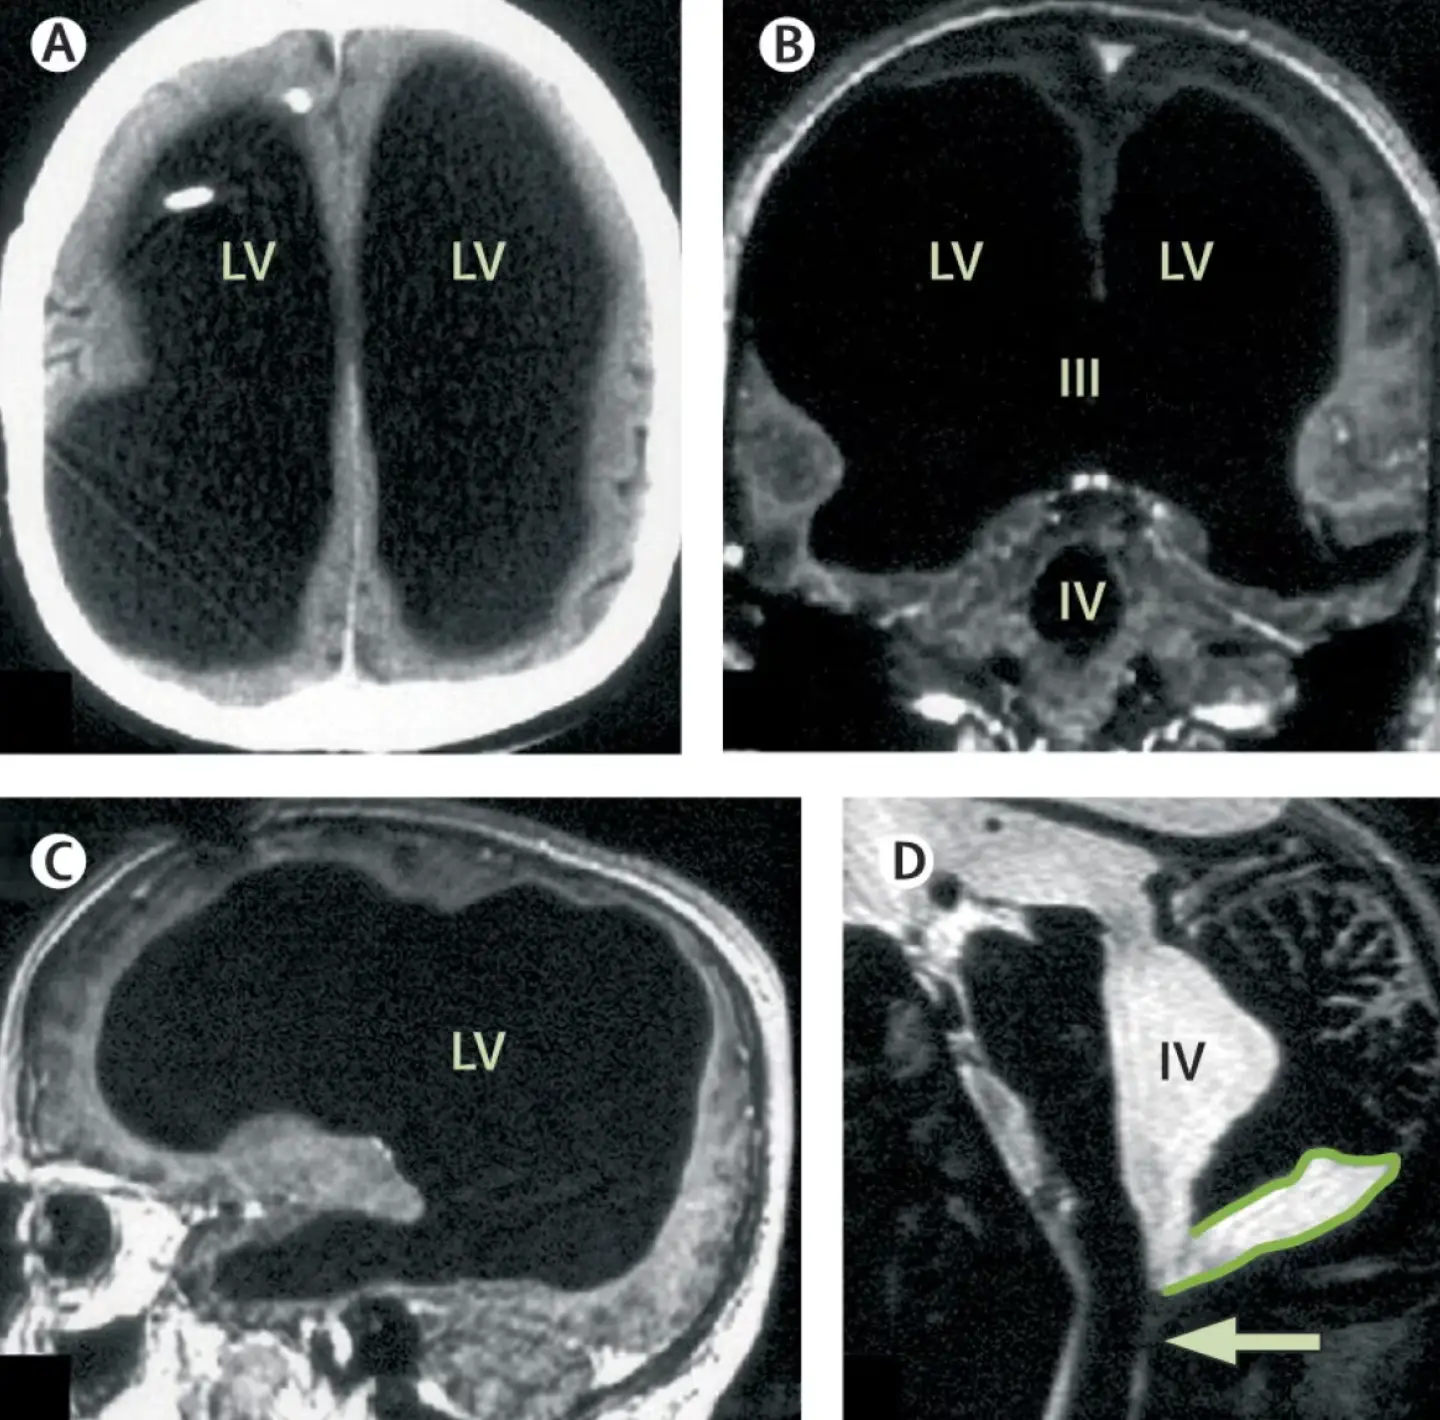

Following an MRI, the scans shown that most of the mans skull was filled with fluid, instead of brain tissue.

While it was initially thought that brain tissue had eroded, scientists now believe that it was compressed by the fluid.

The brain tissue was compressed into a thin outer layer along the edges of his skull, leaving 90 percent of the skill filled with fluid, instead of brain matter.

The condition is the result of hydrocephalus, a disorder involving the build up of fluid in the brain.

Over time, the fluid slowly accumulated again and seemingly compressed his brain tissue.